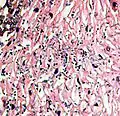

A severe case of candidiasis

In most cases, the diagnosis is established based on response to therapy. Patients in whom esophageal candidiasis is suspected should receive a brief course of antifungal therapy with fluconazole. If the infection resolves after treatment with fluconazole, then the diagnosis of esophageal candidiasis is made and no further investigation is needed. However, if the infection persists or if there are other factors involved which may warrant further investigation, then patient will undergo an esophagogastroduodenoscopy if it is safe to do so. Endoscopy often reveals classic diffuse raised plaques that characteristically can be removed from the mucosa by the endoscope. Brushing or biopsy of the plaques shows yeast and pseudohyphae by histology that are characteristic of Candida species.